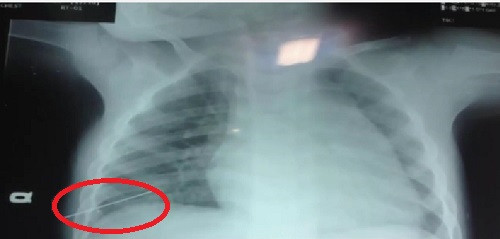

| Hình ảnh chiếc kim khâu đâm xuyên lồng ngực cháu C. trước đó (khoanh đỏ). |